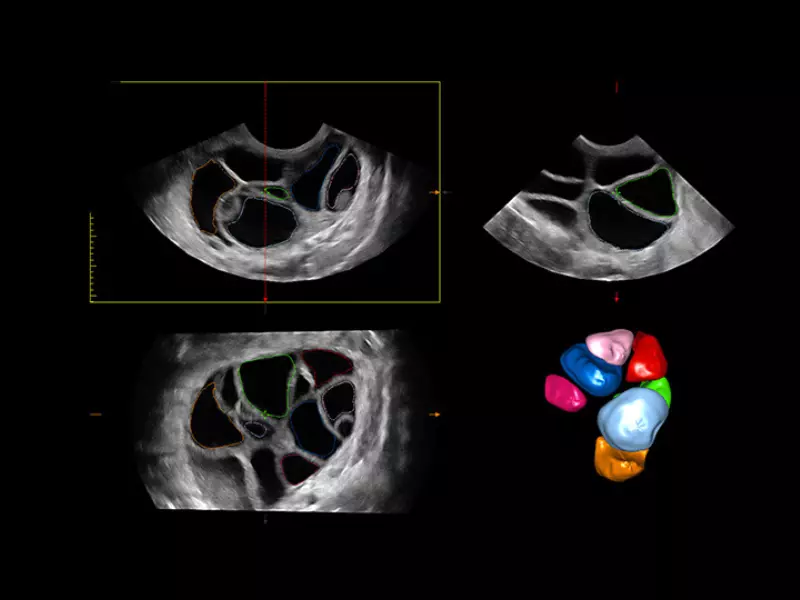

MyLab™9 Platform - XStrain4D technology for volumetric heart assessment by coronary territories

MyLab™9 Platform - XStrain4D technology for volumetric heart assessment by coronary territories